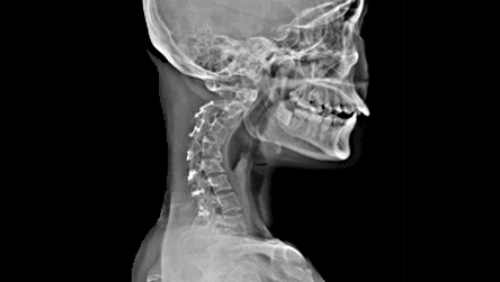

Для оценки состояния тканей в пораженной области назначается магнитно-резонансная томография (МРТ) — наиболее эффективный метод диагностики. Однако существуют и другие способы обследования:

- Рентгенография в двух проекциях, позволяющая получить детальную информацию о наличии искривлений.

- Контрастная миелография — применяется, когда МРТ провести невозможно.